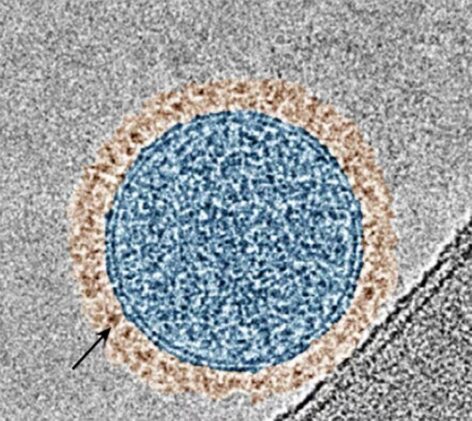

Columbia University engineers report an inhalable therapy designed to dismantle that resistance directly in lung tissue. The system uses exosomes, nanoscale vesicles the body already produces, to carry two therapeutic proteins simultaneously. One blocks the PD-1 or PD-L1 checkpoint pathway that silences T cells. The other interferes with Wnt or beta-catenin signaling, which physically excludes immune cells from entering tumors. The work, led by biomedical engineer Ke Cheng, appears in Nature Biotechnology.

Standard antibody drugs circulate through the bloodstream and may not reach tumors in the right proportions or at the same time. By co-displaying both proteins on a single exosome using a sorting domain called Alix, the researchers ensured each carrier delivers a coordinated signal in a precise one-to-one ratio. When inhaled, the engineered exosomes stick to lung tissue far better than intravenous antibodies, concentrating exactly where metastases tend to form.

Immune checkpoint inhibitors work by releasing molecular brakes that normally prevent immune cells from attacking healthy tissue. Cancer cells exploit those same brakes to avoid detection. When tumors develop resistance, they often activate additional suppression pathways, creating a layered defense. The BEAT system, short for bispecific exosome activator of T cells, addresses this by simultaneously cutting the brakes on immune cells and opening the locked doors that keep them from reaching tumors.